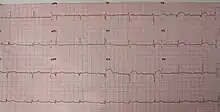

A left ventricular aneurysm can be associated with ST elevation.[2]

When a person visits the hospital or doctor with other symptoms, especially with a history of heart problems, they will normally be required to undergo an electrocardiogram, which monitors electrical activity within the heart and shows abnormalities when a cardiac aneurysm is present. It can also appear as a bulge on a chest x-ray, and a more accurate diagnosis will then be made using an echocardiogram, which uses ultrasound to 'photograph' the heart and how it functions while it beats.

Blood thinning agents may be given to help reduce the likelihood of blood thickening and clots forming, along with the use of drugs to correct the irregular rhythm of the heart (seen on the electrocardiogram)